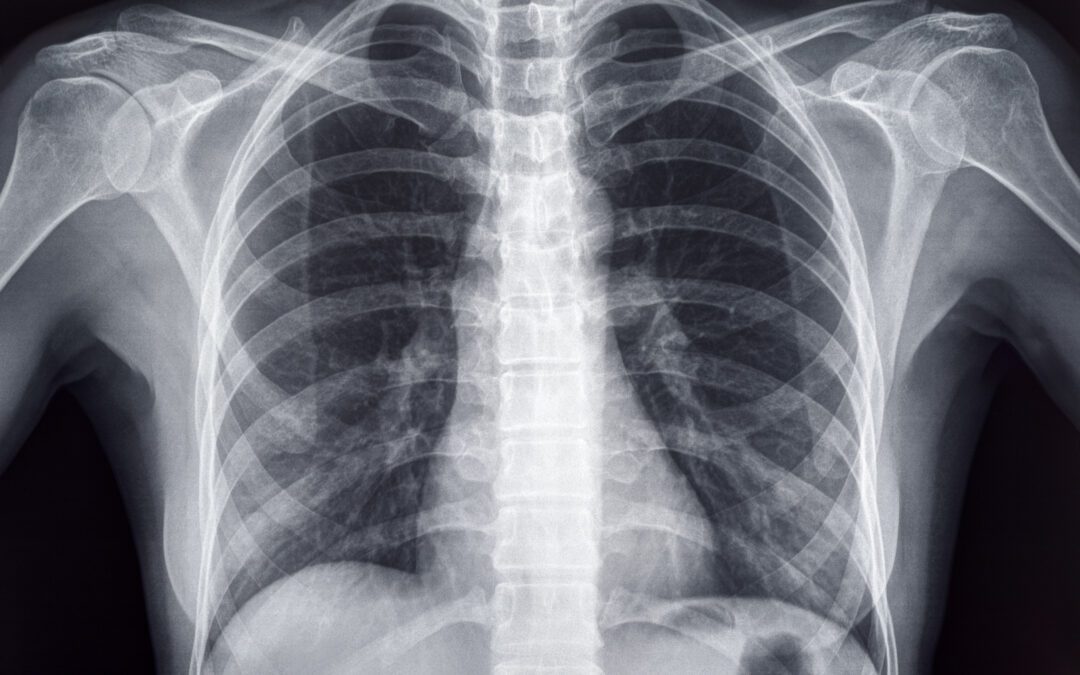

Patients who come to the Hollywood Diagnosticss Center, or any doctor’s office or medical facility for an X-ray are probably used to having a lead apron draped over them for safety. Studies show this might not be entirely necessary. This shift in the guidelines...